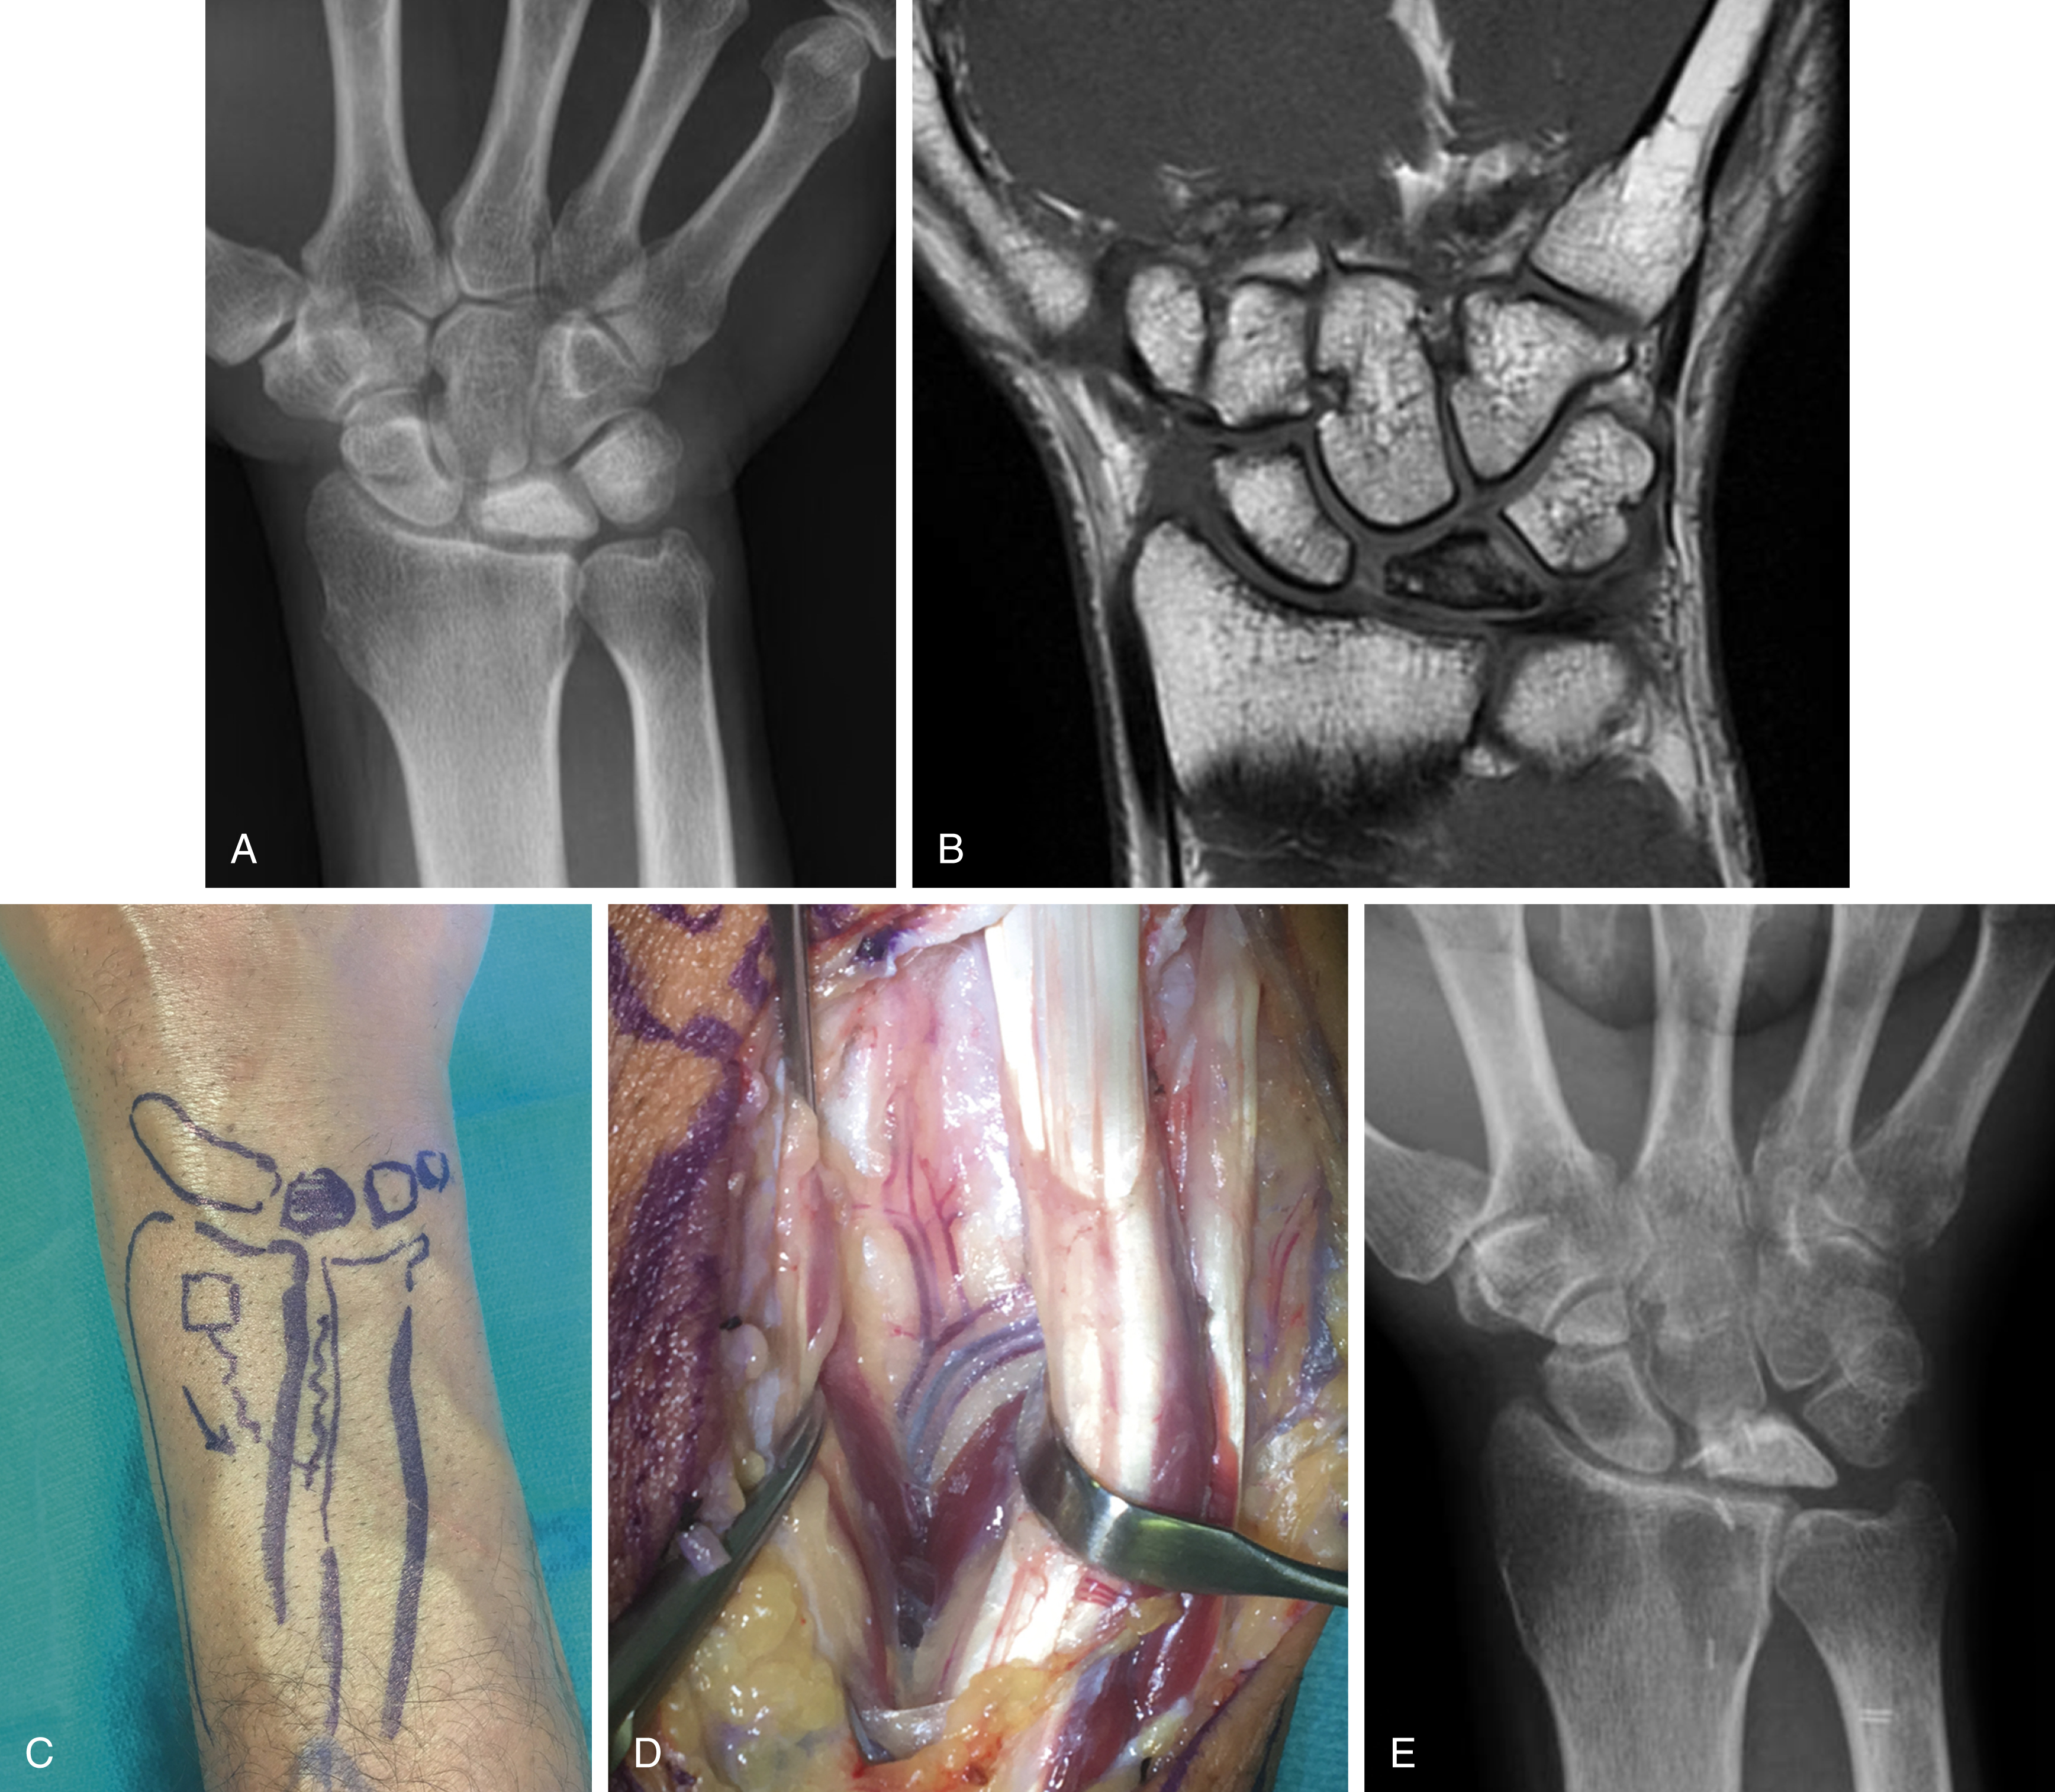

Revascularization procedures are most appropriate in stage II and IIIA with ulnar positive or neutral variance. A number of revascularization procedures have been described, including vascularized pedicle transfer from the distal radius, vascularized pisiform transfer, vascularized bone graft from the metacarpal, and free vascularized grafts from the iliac crest, medial femoral condyle or medial femoral trochlea. The most popular vascularized pedicle transfer is from the distal radius and is the 4,5 extensor compartment artery (ECA) ( Fig. 58.1 ). In more advanced disease, coronal fractures of the lunate can be fixated in preparation for a vascularized osteochondral graft. These procedures may be accompanied by joint leveling procedures such as capitate shortening, radius osteotomy or external fixation.

Treatment of scaphoid nonunions with avascular necrosis of the proximal pole have been most successfully treated with vascularized bone grafts. The most popular vascularized bone graft is the 1,2 intercompartmental supraretinacular artery (1,2 ICSRA) bone graft taken from the dorsal aspect of the distal radius. The vascular anatomy of the 1,2 ICSRA is consistent, but very small. Recent reports have shown about a 75% union rate with use of the 1,2 ICSRA vascularized graft. A capsular-based vascularized bone graft has been described by Sotereanos et al and based off the artery of the base of the fourth dorsal compartment. This technique has been praised for its simplicity. However, both these techniques provide only a small amount of bone for reconstructing a humpback deformity and the vascular pedicles are tenuous. Recently, free vascularized bone grafts taken from the medial femoral condyle (MFC) or trochlea (MFT) and based off either the longitudinal (MFC) or transverse (MFT) branches of the descending geniculate artery has been described. The free vascularized medial femoral condyle flap can be taken without articular cartilage or with articular cartilage as a medial femoral trochlea flap utilizing the transverse branch of the descending geniculate artery, with or without a chimeric skin paddle. The vascular pedicle of these flaps is sufficiently robust and is usually anastomosed end-to-side into the radial artery in the anatomical snuffbox or volar wrist. The donor sites of each of these flaps appear to be well tolerated, with patients returning to normal lower extremity function ( Fig. 58.2 ). In the setting of proximal pole avascular necrosis, we prefer to core out the proximal pole bone, preserving the cartilaginous cap and the scapholunate ligament, and place the bone graft as a dowel into the scaphoid.